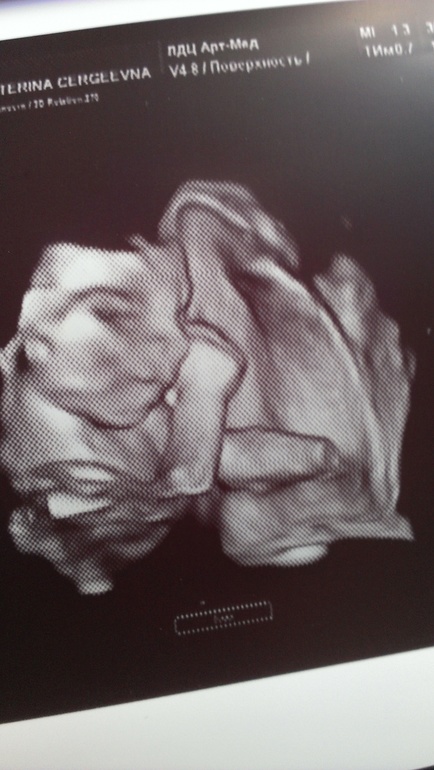

А еще мы узнали, что у нас будет девчушка :))) Вот такая :)